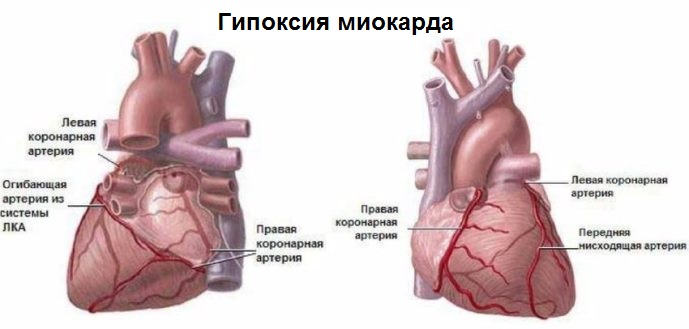

Анатомия коронарных артерий: КТ-изображения

Раздел: Снимки успеха